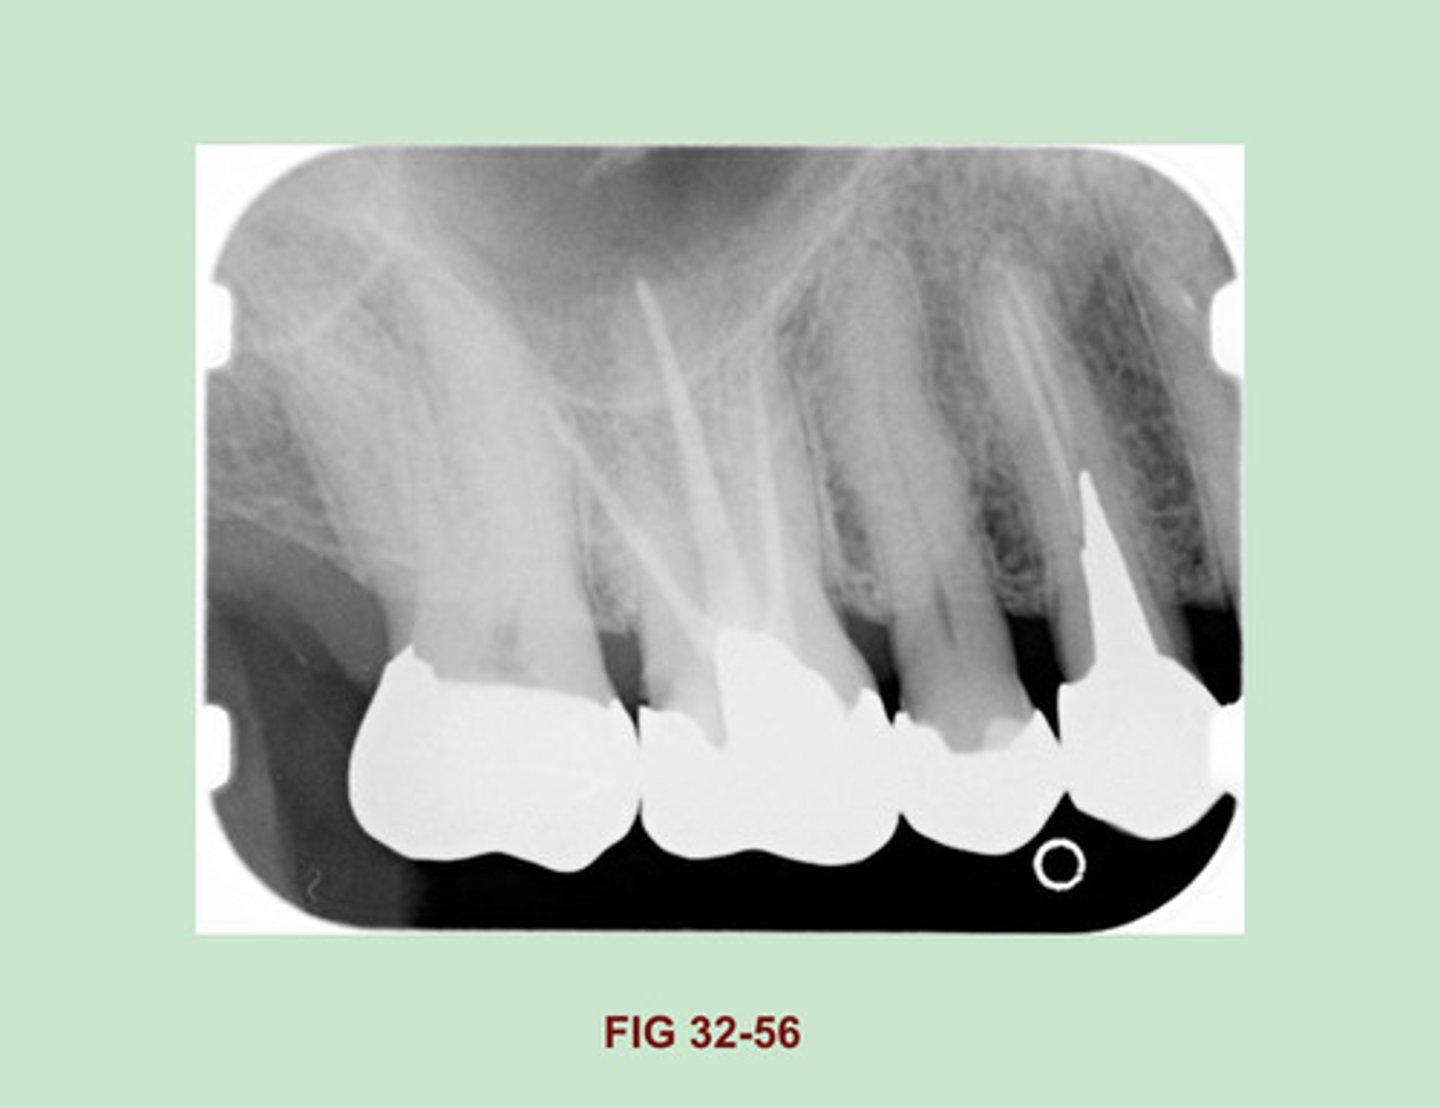

Identify the RESTORATIVE material used in the PULP CANAL of the maxillary first molar (Figure 32-56).

Gutta Percha

Side Note: Gutta Percha is a RUBBERLIKE material used in endodontic therapy to fill the canals of the pulp. Gutta percha appears radiopaque, similar in density to that of base materials (Figure 32-31). Compared w/ metallic restorations, gutta percha appears LESS radiopaque.